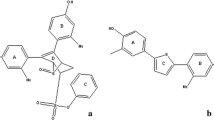

In order to obtain reliable QSAR models, molecular alignment is considered as one of the most sensitive parameters (Cho and Tropsha 1995; Thaimattam et al. 2005). In this study, the most potent compound was selected as a template, and the remaining compounds were aligned on the template by common substructure alignment (as shown in Figs. 1a and 2a). And three different alignment rules were employed to build the most reliable QSAR models: template ligand-based alignment, docking-based alignment, and scaffold-based alignment.

Template ligand-based alignment (Alignment 1): in this method, the most potent compound (compound 11 for ERβ and compound 78 for ERα) was selected as template to align the remaining compounds. The aligned results are shown in Figs. 1b and 2b.

The CoMFA steric contour map is shown in Fig. 4a, where the sterically favorable regions are represented in green and the unfavorable regions in yellow. A small green contour map located at the fluorine atom of ring A (Fig. 1a) indicates that bulky substituent is favored at this position, as illustrated by the fact that the inhibitory activity of compound 11 (F) is stronger than that of compound 10 (H), the same as compound 13 (F) and compound 12 (H). Another green contour map is covered the para position of ring D, indicating that this position is suitable for larger substituent. The higher activity of compound 22 (–CH2CH(CH3)2) than compound 20 (i-Pr) is an example. A large green contour is mapped near ring E, illustrating that bulkier group at this position may increase the activity, as illustrated by the fact that the pIC50 value of compound 59 ( ) is higher than that of compound 58 (

Similar to ERβ models, the most potent compound 78, which represents the general structure of the inhibitors was selected to analyze the contour maps.

According to the QSAR and molecular docking results, the key structural features influencing the selectivity can be obtained. The structure–activity relationship is summarized (Fig. 15) as follows: (1) electropositive and hydrophilic groups at ring A, bulky, electronegative, and hydrophobic groups at ring D, electropositive and hydrophilic groups at ring E would be beneficial to the ERβ and ERα binding activity. (2) In addition, the differences are also appeared in the contour maps. ERβ has a green contour map around ring A while ERα is yellow here, which means that the binding activity of ERα can be improved by minifying the volume of the substituent at ring A. Another difference existed at the terminal position of ring F for ERα, the color is green for ERβ but yellow for ERα, further indicating that steric interaction is favorable for ERα, and unfavorable for ERβ.